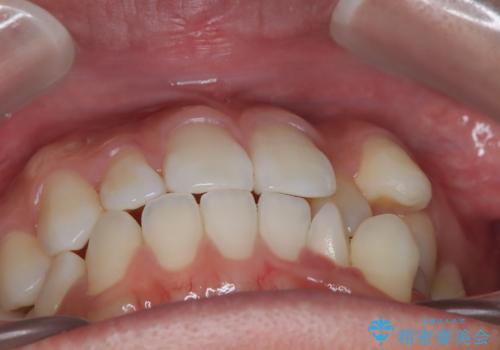

- 治療計画

- 八重歯と前歯のガタつきを主訴として来院されました。診査の結果、歯列全体の叢生量が大きく、上下左右の第一小臼歯4本の抜歯が必要と判断。審美性にも配慮し、白いブラケットとメタルワイヤーを用いたクリア矯正装置での治療を選択しました。治療期間はおよそ1年半を見込んで計画しました。

上下左右の第一小臼歯を抜歯し、クリアブラケット(白い装置)とメタルワイヤーを使用して矯正を開始。初期には犬歯のアーチ内への整列を優先し、中盤からは前歯と奥歯の咬合関係の調整を進めました。審美性に優れた装置を使用したことで、治療中も目立ちにくく、見た目へのストレスが少ない点も評価されています。全体の治療は1年半で完了し、見た目・噛み合わせともに大きく改善。患者本人も「短期間でここまで変わるとは思わなかった」と満足されていました。